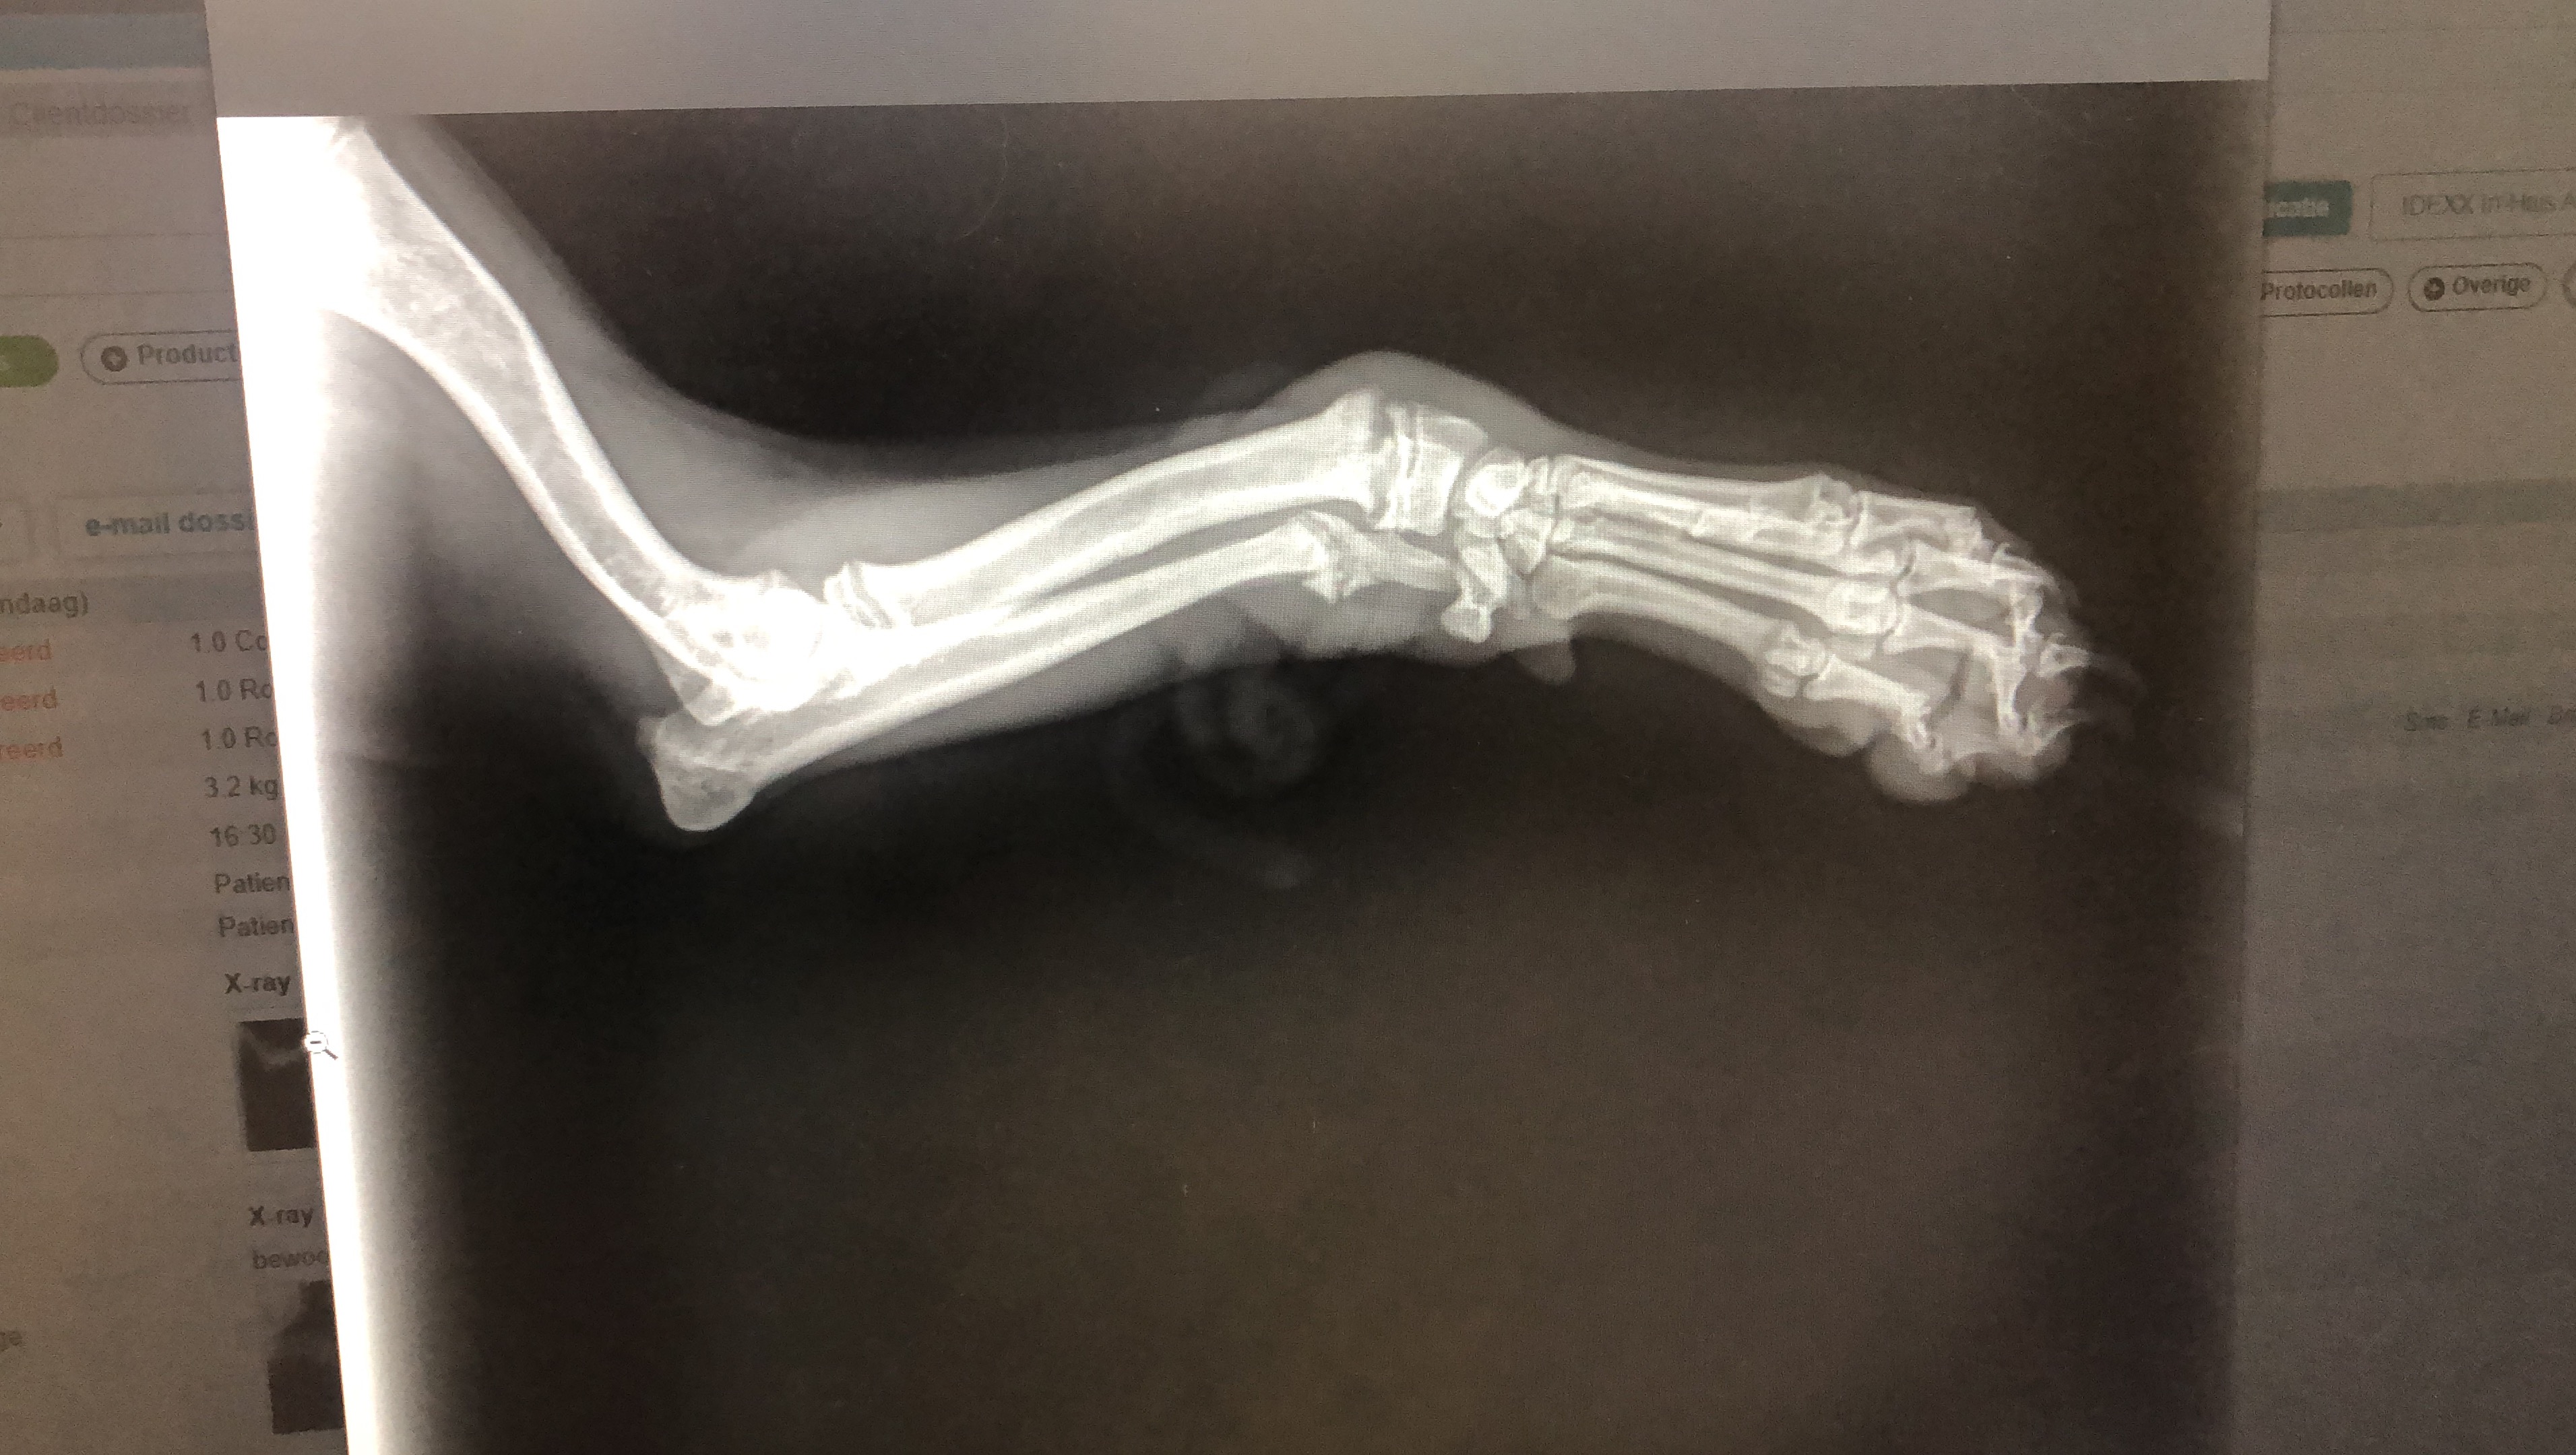

Mijn naam is Maureen. Grote dierenliefhebber. Graag heb ik financiële hulp nodig voor een eenzame vrouw en haar hondje Milo. Woensdag 26-02-2025 is Milo van de bank gevallen en schreeuwde het uit van de pijn. Donderdag had ik contact met mevrouw en ben ik samen met mijn collega Cindy vanuit Heerlen naar Papendrecht gereden.

Helaas is zijn pootje niet meer te redden. Milo is 5 maanden.

Inmiddels is Milo geopereerd en zijn voorpoot geamputeerd.